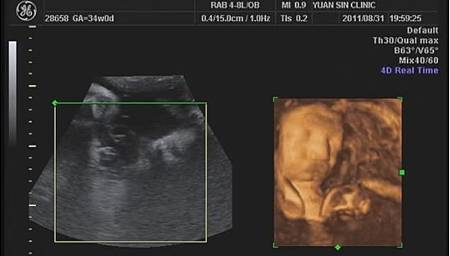

第八次產檢--寶寶34W

2011.08.31 第八次產檢了...小乖34W

今天又要抽血...還有乙型鏈球菌篩檢...

另外也得做NST看一下宮縮狀態有沒有減緩...

雖然沒有之前爆表的宮縮...但是還是有亂七八糟的宮縮...